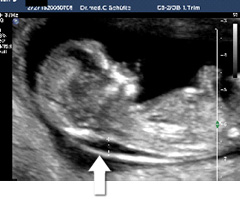

Messung der Nackentransparenz

Dieses Bild zeigt eine unauffällige

Nackentransparenz.